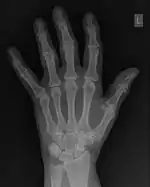

FFTs can also be calculated in two-dimensions to give results such as those in Figure 1.27. Since Fourier analysis generates results in terms of both positive and negative spatial frequencies, these can be plotted in the form of a 2D image so that the maximum frequency lies at the origin and those for the horizontal and vertical directions are shown increasing towards that origin. The modulation at different spatial frequencies is represented using a grey-scale. Low frequency bands can be seen along the horizontal axis in the figure, for example, representing the horizontal periodicity of image data from the fingers, while finer bands along the y-dimension are indicative of a periodicity of image data from the various metacarpophalangeal joints. Higher frequency features can also be seen running diagonally in this 2D-FFT, representative of the trabecular structure of the bones, for example.

The essence of this approach is that it can be used to produce a range of image processing effects by enhancing and/or suppressing features in the 2D-FFT and then converting the result back into the spatial domain using the IFT, as illustrated in Figure 1.28. Such image manipulations are considered in more detail in a later chapter. Note that the form of image processing demonstrated in the figure is for purely illustrative purposes and bears no direct medical significance.

![]() Fig. 1.28(a): A radiograph of the wrist. | ![]() Fig. 1.28(b): The wrist radiograph processed by attenuating periodic structures of size between 1 and 10 pixels. |

![]() Fig. 1.28(c): The wrist radiograph processed by attenuating periodic structures of size between 5 and 20 pixels. | ![]() Fig. 1.28(d): The wrist radiograph processed by attenuating periodic structures of size between 20 and 50 pixels. |